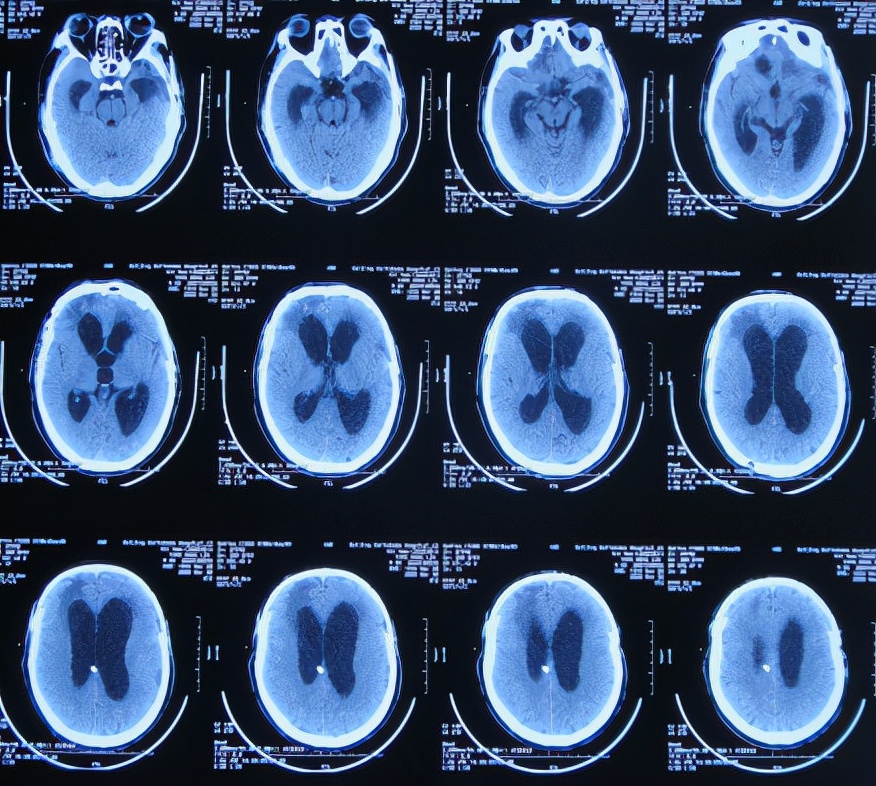

继续治疗1周时间内,曾3次复查头颅CT( 图-5、图-6、图-7 )均示脑膨出逐渐加重的趋势,仍有积血;期间给予腰大池引流。

图-5: 2019年10月26日头颅CT

图-6: 2019年10月29日头颅CT

图-7: 2019年10月31日头颅CT

开颅术后14天即2019年11月3日,虽仍有些积血,但脑膨出有好转( 图-8 ),意识也变清。

图-8: 2019年11月3日头颅CT

开颅术后18天即2019年11月7日,脑膨出进一步好转( 图-9 )。

图-9: 2019年11月7日头颅CT

开颅术后26天即2019年11月15日,查头颅CT示积血基本消失,脑膨出变正常( 图-10 )。

图-10: 2019年11月15日头颅CT

开颅术后30天即2019年11月19日,出现走路不稳,查颈椎核磁( 图-11 )后认为无明显异常。

图-11: 2019年11月19日腰椎核磁

开颅术后33天即2019年11月21日,查头颅CT( 图-12 )后认为无明显异常随后出院。

图-12: 2019年11月21日头颅CT